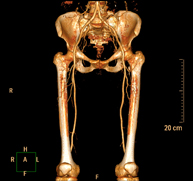

- Aortoiliac CT angiography

A non-invasive diagnostic test that involves examining the iliac arteries and abdominal aorta, obtaining high-definition anatomical images using CT (computed tomography) equipment and iodinated contrast dye. With the aid of workstations specialised for arterial studies, the image quality supports 2D and 3D reconstructions. This test is particularly recommended as a pre-surgical study (vascular map) prior to percutaneous or surgical interventions on the abdominal aorta, as a complementary study in patients with lower limb ischaemia, etc.